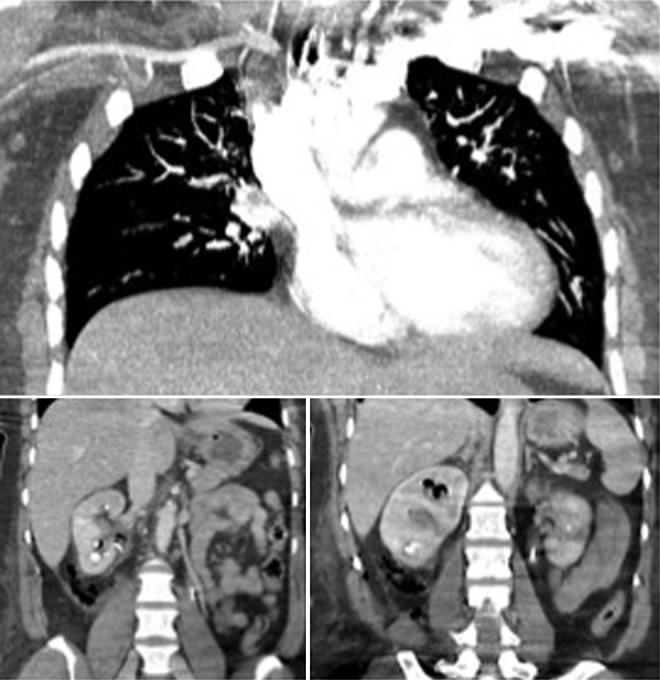

Hydrogen peroxide (HO) is a common antiseptic that is available without a prescription in the United States, and it is indicated for minor dermal abrasion; mouth, gum, or dental irritations; and removal of oral secretion. Several other medical uses have also been described, including clot dissolution during endoscopic gastrointestinal evaluation, cleansing of orthopedic surgical sites, and bladder irrigation. However, these uses of HO, as well as high-dose ingestion, have been associated with a wide variety of medical complications, including but not limited to air pulmonary embolism and stroke. Our patient is a 51-year-old female with a medical history of hypertension, familial, hypercholesterolemia, gallstones, depression, coronary artery disease (identified on calcium study because of familial hypercholesterolemia), nephrolithiasis, and recurrent cystitis. She required percutaneous nephrolithotomy and had HO administered for clot dissolution. The clinical and temporal evidence would suggest a transient pulmonary air embolus after the intrarenal administration of or irrigation with HO, large amounts under high pressure. This represents the first reported incidence of air embolus as a result of intrarenal administration of HO.

过氧化氢(HO)是一种常见的防腐剂,在美国无需处方即可获得,适用于轻微皮肤擦伤、口腔、牙龈或牙齿刺激以及清除口腔分泌物。还描述了其他一些医学用途,包括在内镜胃肠道评估期间溶解血凝块、清洁骨科手术部位和膀胱冲洗。然而,HO的这些用途以及高剂量摄入与多种医学并发症有关,包括但不限于空气肺栓塞和中风。我们的患者是一名51岁女性,有高血压、家族性高胆固醇血症、胆结石、抑郁症、冠状动脉疾病(因家族性高胆固醇血症在钙研究中确诊)、肾结石和复发性膀胱炎病史。她需要进行经皮肾镜取石术,并接受HO以溶解血凝块。临床和时间证据表明,在高压下大量经肾内给药或冲洗HO后出现了短暂的肺空气栓塞。这是首次报道经肾内给药HO导致空气栓塞的病例。